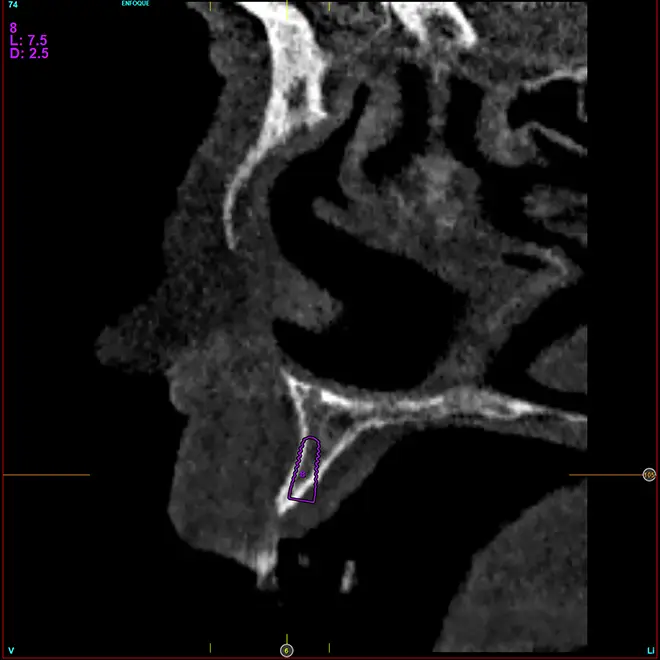

En la zona correspondiente a la pieza 24, tenemos una atrofia extrema también pero en este caso en sentido vertical, con una cresta residual de 3,1 mm de grosor, como podemos ver en el corte seccional del cone-beam (fig. 11). En este caso se planifica la colocación de un implante de 2,5 mm de diámetro y 6,5 mm de longitud (con plataforma reducida de 3 mm -plataforma 3.0, biotechnology institute-) (fig. 12). Igualmente, en la zona anterior de la premaxila, tenemos una situación muy similar donde el volumen óseo es reducido, incluso más que en la zona del segundo cuadrante y, por ello, optamos también por implantes de 2,5 mm de anchura y plataforma de 3 mm (figs. 13-16).

Fig. 11. Corte de planificación de la zona correspondiente a la pieza 24, que presenta una atrofia ósea en anchura extrema con 3,1 mm de anchura residual.

Fig. 12. Planificación del implante de 2,5 mm de diámetro y 6,5 mm de longitud que será colocado en la zona.